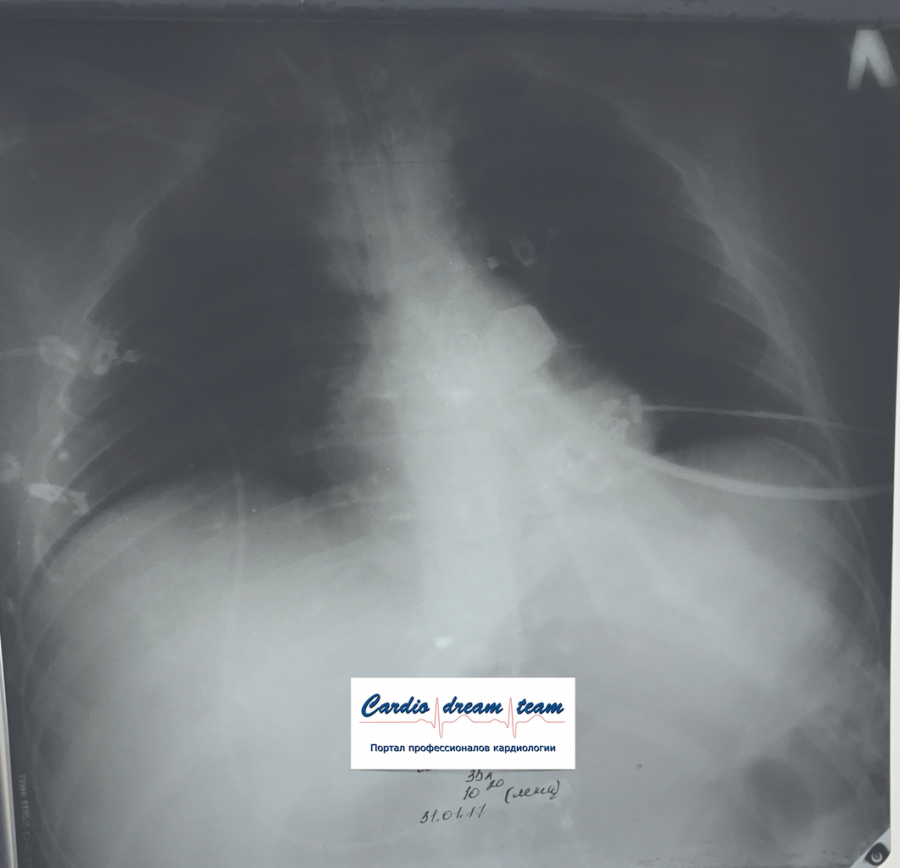

М 35 лет наркоман. Аспирация рвотных масс. До санации и после.

IMG_6456.png

IMG_6456.png [ 1.17 MiB | Просмотров: 12424 ]